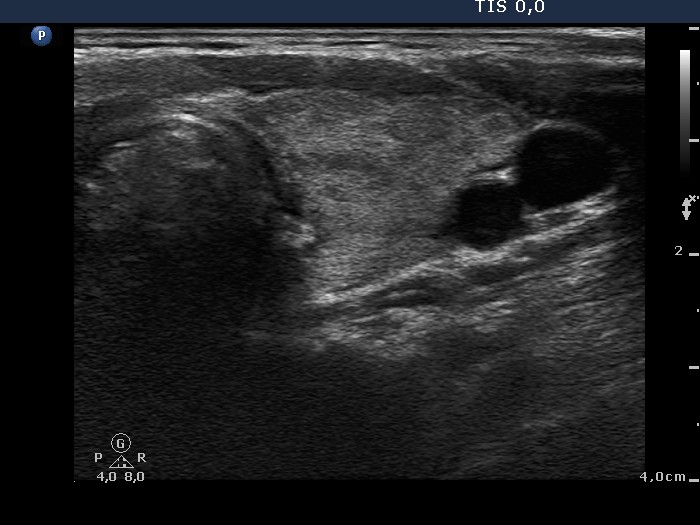

Graves' disease - Case 1049

Follow-up investigation 33 months after first visit (ultrasonographic picture 4)

Patient on daily 20 mg methimazole therapy in euthyroid state

Left lobe, transverse view. Great part of this lobe is echonormal.